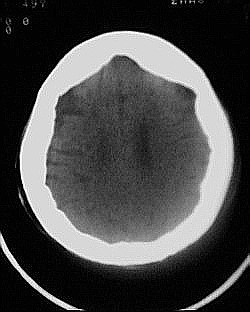

患者/49y/ 女/4年前有脑梗, 现因右侧肢体无力来院做ct扫描 ! 老师们看看这骨头有事吗?钙化点是什么原因呀??

1.颅骨对称性、形态规整性增厚,应属发育异常。四叠体池左后侧单发点状钙化,无其他阳性表现,多属正常,不需要过多关注。

2.双侧基底节区域多发性梗塞灶。

可能为颅骨内板增生症,以额骨多见,常见于女性.多无临床意义.部分病人可有头痛.可找相关资料看看.

颅骨内板增厚,密度稍减低,未见明显破坏,考虑为正常。(检查老年人时遇到过类似颅骨未报病变,谁有相关资料请上传学习)

2.颅骨内外板广泛性增厚,板障狭窄甚至消失,双侧对称。无明显相应临床症状。考虑“泛发性骨皮质增厚症”。可进一步检查下颌骨及管状骨骨干。(下颌骨骨小梁增多、密集,密度增高亦为本病特点,管状骨骨干皮质向内增厚引起骨皮质厚度增加,骨密度增浓、髓腔狭窄但不消失,骨干周径较少增加)。与石骨症鉴别,后者很少影响颅盖骨和下颌骨,管状骨改变主要累及干骺端和骨骺,而骨干皮质较少增厚,椎体和髂骨翼有特征性表现。

“泛发性骨皮质增厚症,又称骨内膜增生症(endosteal hyperostosis):分为常染色体隐性遗传性疾病(van buchem)和常染色体显性遗传性骨硬化症(worth病)。后者更少见,亦较轻。两者的病理上均为骨内膜 成熟的板状新生骨形成,髓腔变窄。颅骨、颅底骨 、下颌骨,肋骨、四肢骨及骨盆骨、脊柱均可见骨内膜增生,髓腔变窄或消失,但骨外径不加大,骨骺不累及。”

本例的确应该这个病。建议楼主检查病人其他部位有无类似表现,以便确诊。